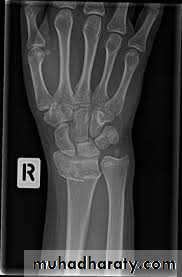

The patient presents with a wrist injury, but there is no dinner-fork deformity. Instead, there is a ‘garden spade’ deformity.X-ray

There is a fracture through the distal radial metaphysis; a lateral view shows that the distalfragment is displaced and tilted anteriorly – the

opposite of a Colles’ fracture.